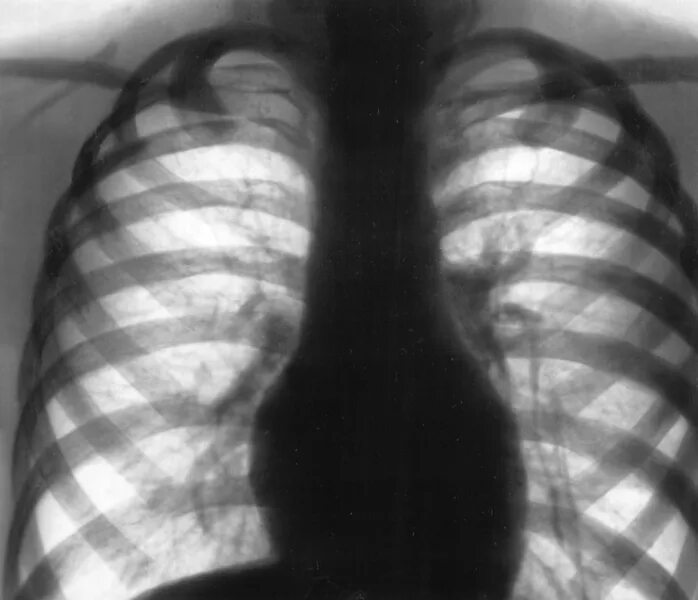

Как лечить пневмосклероз легких в пожилом возрасте